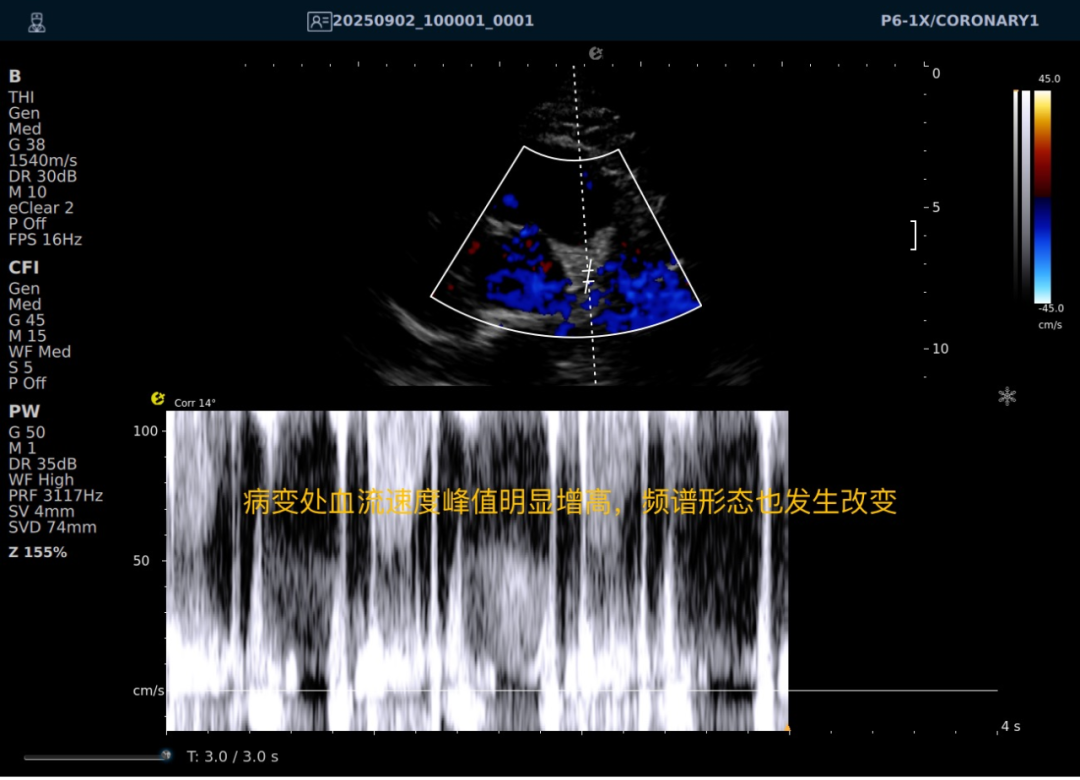

一例胸闷患者,临床采用无创冠脉超声作为初步评估手段,检查中发现:

彩色多普勒:敏感捕捉到局部血流加速现象;频谱多普勒:测得峰值血流速度明显升高,频谱形态异常。

彩色多普勒动态图

彩色多普勒

频谱多普勒

基于超声提示的异常发现,临床为患者安排了冠脉CTA检查,结果显示前降支近段存在约45%狭窄,与超声提示的血流动力学改变高度一致。

这一病例体现了冠脉超声作为初筛工具的重要价值:它能够无创、实时地评估冠脉血流动力学状态,为后续是否需要进一步影像检查提供重要参考。超声与CTA的协同应用,既能评估结构变化,又能反映功能状态,为临床诊断提供了更全面的信息。